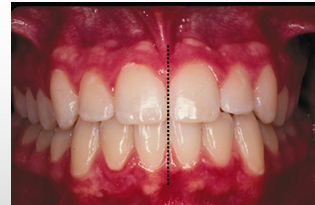

midline assessments

1) maxillary midline to facial midline

2) intermaxillary midline

3) mandibular midline to facial midline

intermaxillary dental midline

-maxillary dental midline: a line drawn perpendicular to the maxillary occlusal plane through the proximal contacts of the central incisors

-mandibular dental midline: a line drawn perpendicular to the mandibular occlusal plane through the proximal contacts of the central incisors

-if deviation- must say what direction and by how much

facial and dental midlines

-maxillary midline to facial midline: determine if maxillary midline lines up with facial midline

-mandibular midline to facial midline: determine if mandibular midline lines up with facial midline